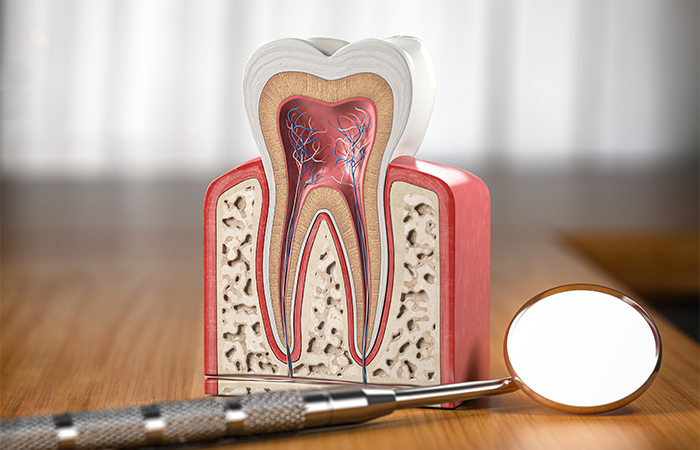

根管治療とは、歯の神経が通る根管内にまで到達したむし歯の治療のことです。むし歯が悪化すると根管内にある歯髄といわれる神経や血管などが炎症を起こします。ひどく痛むだけではなく、やがて全身の健康にも影響を与えます。

根管治療では、最初に汚染された歯髄を取り除く治療を行ってから、根管内をきれいに掃除して無菌状態にしてから閉じます。

歯科用顕微鏡である「マイクロスコープ」は、最大20倍まで視野を拡大することができる機器です。

根管内は暗く非常に複雑な形状をしています。マイクロスコープを使用することで、狭い歯の内部をしっかり見ながら治療を行えるので、感染部分の取り残しを防ぐことができます。

まず、細菌に汚染された歯の神経や血管を丁寧に取り除きます。

局所麻酔を行ってむし歯を削り、歯の神経があらわれたらファイルという針のような器具を使って神経を除去する治療です。

神経を除去してから空洞になった根管を拡大し、殺菌力の強い薬剤を使用して歯の内部を丁寧に消毒します。根管は複雑な形状をしているため、根管拡大は高度な技術が必要な治療です。

また、汚染された神経が残ると再発の恐れがあるため、感染した歯質などもしっかり取り除きます。

根管内を十分に消毒・洗浄したら、細菌が繁殖してむし歯が再発するのを防ぐために、空洞になった根管内に特殊な薬剤でできた根管充填材をすき間なく詰め込みます。